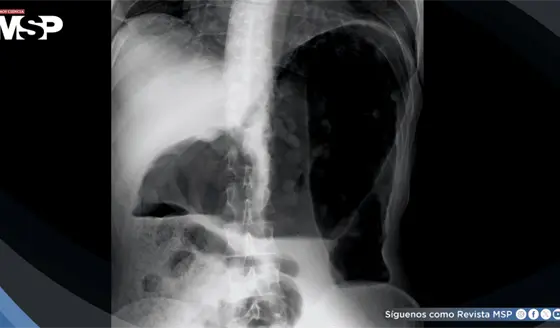

El doctor Chinea lo explicó: "Podemos diagnosticar pacientes antes de que aparezca la enfermedad", añadió que "tenemos ejemplo de pacientes que hemos podido diagnosticar porque por incidencia se le hace una resonancia magnética y vemos que hay lesiones".

Para detectar este proceso oculto y dañino, la ciencia se apoya en biomarcadores en sangre y en técnicas avanzadas de resonancia magnética, que pueden medir con precisión la pérdida de volumen cerebral y predecir si la enfermedad podría volverse más agresiva.